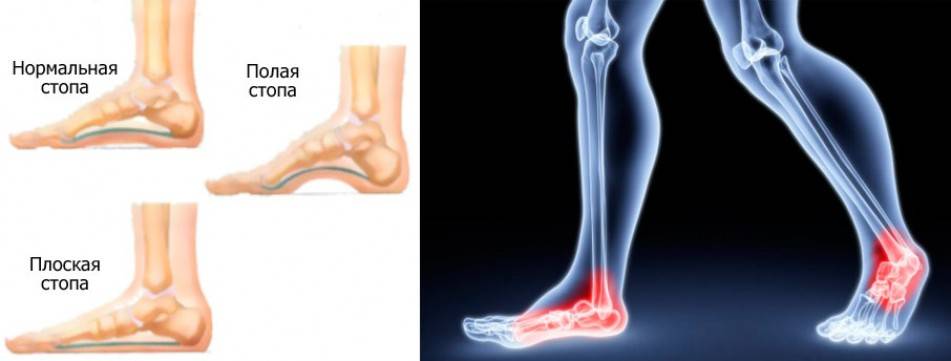

Плоскостопие

Наиболее распространенное деформационное изменение, поражающее одну либо обе стопы, проявляющееся в опускании свода, на фоне которого исчезает «арка».

Эта патология влечет за собой и другие последствия. У человека, страдающего от плоскостопия, механика коленных суставов начинает работать иным образом.

Это меняет распределение нормальной нагрузки, походка становится другой, осанка ухудшается.

Деформация стопы проявляет себя при подборе неправильной обуви как для бега, так и для обычной ходьбы. Если пара не является подходящей, то возникает оверпронация ступни, когда перпендикулярное положение оси изменяется, то есть она начинает «заваливаться» внутрь. Проявляется это состояние быстрым изнашиванием внешней части каблуков.

Левая и правая ступни чаще всего имеют различную степень проявления плоскостопия. Это создает некоторый дисбаланс при смещении оси лодыжек, что влечет за собой неравномерную деформацию скелета и перекос фигуры. Чтобы избежать такого неблагоприятного последствия, нужно носить специальную ортопедическую обувь.

Плоскостопие

Наиболее распространенное деформационное изменение, поражающее

одну либо обе стопы, проявляющееся в опускании свода, на фоне которого исчезает

«арка». Эта патология влечет за собой и другие последствия. У человека,

страдающего от плоскостопия, механика коленных суставов начинает работать иным

образом. Это меняет распределение нормальной нагрузки, походка становится

другой, осанка ухудшается.

Тип стопы

Узнайте тип своей стопы, в том числе определите какой у нее подъем: низкий, нормальный или высокий. Если вы не уверены в том, какой у вас тип стопы, то проведите простой тест: окуните ногу в небольшую емкость с водой, затем поставьте стопу на лист бумаги, после чего посмотрите на оставшийся след.

Низкий свод: если стопа отпечаталась почти полностью, то у стопы низкий свод, и, вероятно, во время ходьбы или бега она будет иметь тенденцию склоняться внутрь. В таком случае вам, возможно, необходима обувь с контролем движений или повышенной устойчивостью.

Нормальный свод: если вы видите только половину свода, то у вашей стопы нормальная пронация. Это самый распространенный тип и, скорее всего, вам подойдет большинство моделей обуви.

Высокий свод: если вы увидите только отпечаток подушечки стопы и пятки, то у вашей стопы высокий свод. Вполне возможно, что в данном случае при ходьбе или беге стопа будет иметь тенденцию к повороту наружу. Выбирайте мягкую обувь с повышенной гибкостью, которая позволит более эффективно поглощать удары. Также приобретите специальные стельки для поддержки пятки и свода. Они, как правило, продаются отдельно и имеют различный размер и характеристики.

Пронация стопы

О пронации говорит количество точек соприкосновения стопы с поверхностью пола. Существует 3 основных типа пронации:

При чрезмерной пронации точки соприкосновения смещаются внутрь, а значит возникает риск растяжения мышц стопы и ног. Также при гиперпронации, как правило, у стопы низкий свод. Выбирайте обувь с повышенной устойчивостью и контролем движений, чтобы сгладить такие анатомические особенности стопы.

При недостаточной пронации (супинация) во время ходьбы или бега точки соприкосновения стопы с поверхностью земли смещены наружу. Как правило, в таких случаях у стопы высокий свод. Выбирайте обувь с дополнительной амортизацией, которая позволяет смягчать и поглощать удары.

При нормальной пронации точки соприкосновения распределены равномерно. Выбирайте обувь с повышенной стабильностью, которая является более гибкой по сравнению с кроссовками с контролем движений, но также обеспечивает хорошую поддержку.

Плоскостопия чаще всего бывает два, иногда три. Поперечное, продольное и их комбинация – продольно-поперечное.

Поперечный свод чаще всего уплощается из-за того, что мы носим узкую обувь в области носка и очень часто стараемся как можно выше приподнять пятку. Это, естественно, о женщинах, любящих высокий каблук.

Таким образом, арочка, которая создаёт поперечный свод начинает уплощаться. Плюсневые кости начинают пытаться это компенсировать и разъезжаются, а мягкие ткани компрессируются.

Мы начинаем чувствовать боль в межпальцевых промежутках, потому что нервы зажимаются. У женщин же появляются знаменитые шишки».

Плоскостопием называется уплощение свода стопы, обуславливающее нарушение естественных амортизационных функций. Мнение некоторых людей в том, что бег при плоскостопии противопоказан из-за сильной нагрузки на стопу, ошибочно. Однако при соблюдении некоторых правил эта физическая нагрузка пойдет на пользу.

При плоскостопии происходит деформация и искривление ступней. Естественный изгиб подъема утрачивается, свод стопы опускается вниз. Больные жалуются на усиливающиеся при ходьбе боли в ногах. У женщин после ношения высоких каблуков болят пятки, появляются отеки. Постепенно формируется тяжелая походка, нарушается осанка.

Поперечное плоскостопие хорошо видно по расширенному переднему отделу стопы, подсобранным пальцам, отклонению большого пальца внутрь и очень характерным мозолям.

Продольное плоскостопие можно выявить методом сравнения отпечатков стоп с шаблонами. Отпечаток можно сделать дома, намазав стопу краской и наступив на бумагу. Также диагностику стоп сейчас активно проводят во многих ортопедических салонах.